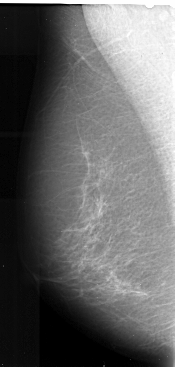

A_1021_1.RIGHT_MLO

FILE: A_1021_1.RIGHT_CC.OVERLAY

TOTAL_ABNORMALITIES 1

ABNORMALITY 1

LESION_TYPE MASS SHAPE ARCHITECTURAL_DISTORTION MARGINS SPICULATED

ASSESSMENT 4

SUBTLETY 3

PATHOLOGY MALIGNANT

TOTAL_OUTLINES 1

BOUNDARY